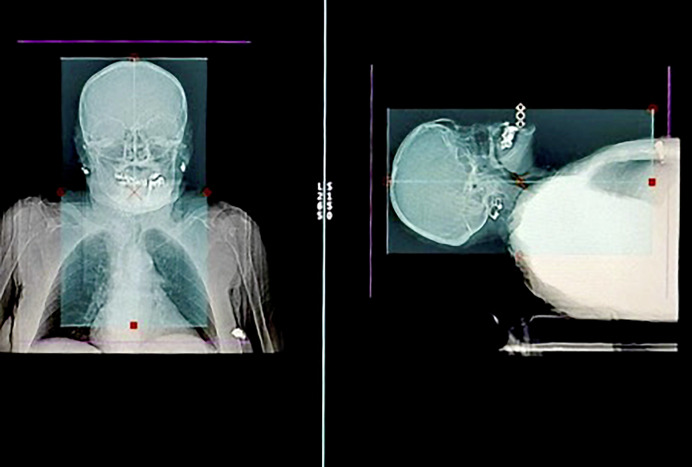

Methods: We extended the CTA scan range of acute stroke patients 4 cm below the carina to include the left atrium and appendage. During the review, we evaluated LAA thrombi based on contrast relations. We then used gradient boosting to identify the most important predictors of LAA thrombi from a variety of different clinical parameters.

Abstract Image